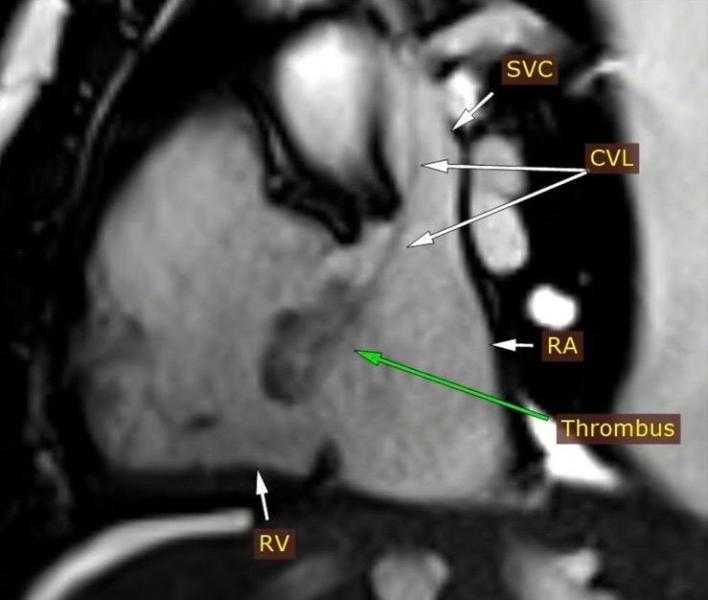

وأضاف الدكتور مجدي القاضي عميد كلية الطب البشري ورئيس مجلس اداره المسشفيات الجامعيه ان التقرير الطبي اوضح بعد إجراء فحوصات الإيكو للقلب، تبين اشتباه وجود ورم بالأذين الأيمن وعلى الفور تم تحويل المريض الى وحدة التصوير الطبى للقلب واجراء رنين مغناطيسى على القلب وتبين ان المريض يعانى من التهابات بعضلة القلب وتواجد جلطة بالاذين الايمن وتم تشخيص الحالة بدقة وتلقى العلاج المناسب بقسم امراض القلب والاوعيه الدمويه.

موكدا، أن الوحدة تعد الأولى من نوعها في إقليم الصعيد، حيث أن هذه الحالة تُعد نموذجًا لما تقدمه وحدة تصوير القلب من خدمات تشخيصية متقدمة، إذ تمكنت من تحديد طبيعة الجلطة ومكانها بدقة عالية، ما ساعد الفريق الطبي في وضع خطة علاج مناسبة أنقذت حياة المريض.